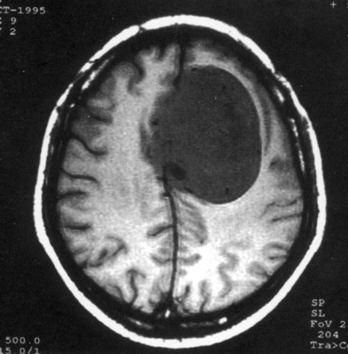

问题 病历摘要:??患者女性,37岁。大便时突起炸裂样头痛3小时,伴喷射样呕吐。既往体健。体检:T37.5℃,BP145/90mmHg,R20次/分,P85次/分。神志清楚,颅神经检查无异常,颈强直,克、布氏征(-),四肢肌力、肌张力正常,病理征(-)。 按Hunt&?Hess的动脉瘤危险性分级,该患者可分为几级?